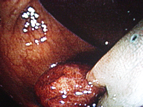

良性の胃ポリープと異なり、大腸ポリープはたとえ現在良性でも将来癌化する可能性があることが知られています。したがってある程度の大きさのポリープは切除することをお勧めします。当院では日帰りで可能ですが

「内視鏡下でポリープ切除が可能」とは言っても、これは手術に該当するものであり、大腸穿孔や術後出血などを引き起こす可能性があります。ポリープを切除した傷が完治するまでの2〜3週間は、食事制限、運動制限、禁酒など合併症予防のために遵守すべき事項があるので、手術を受ける際は厳守して下さい